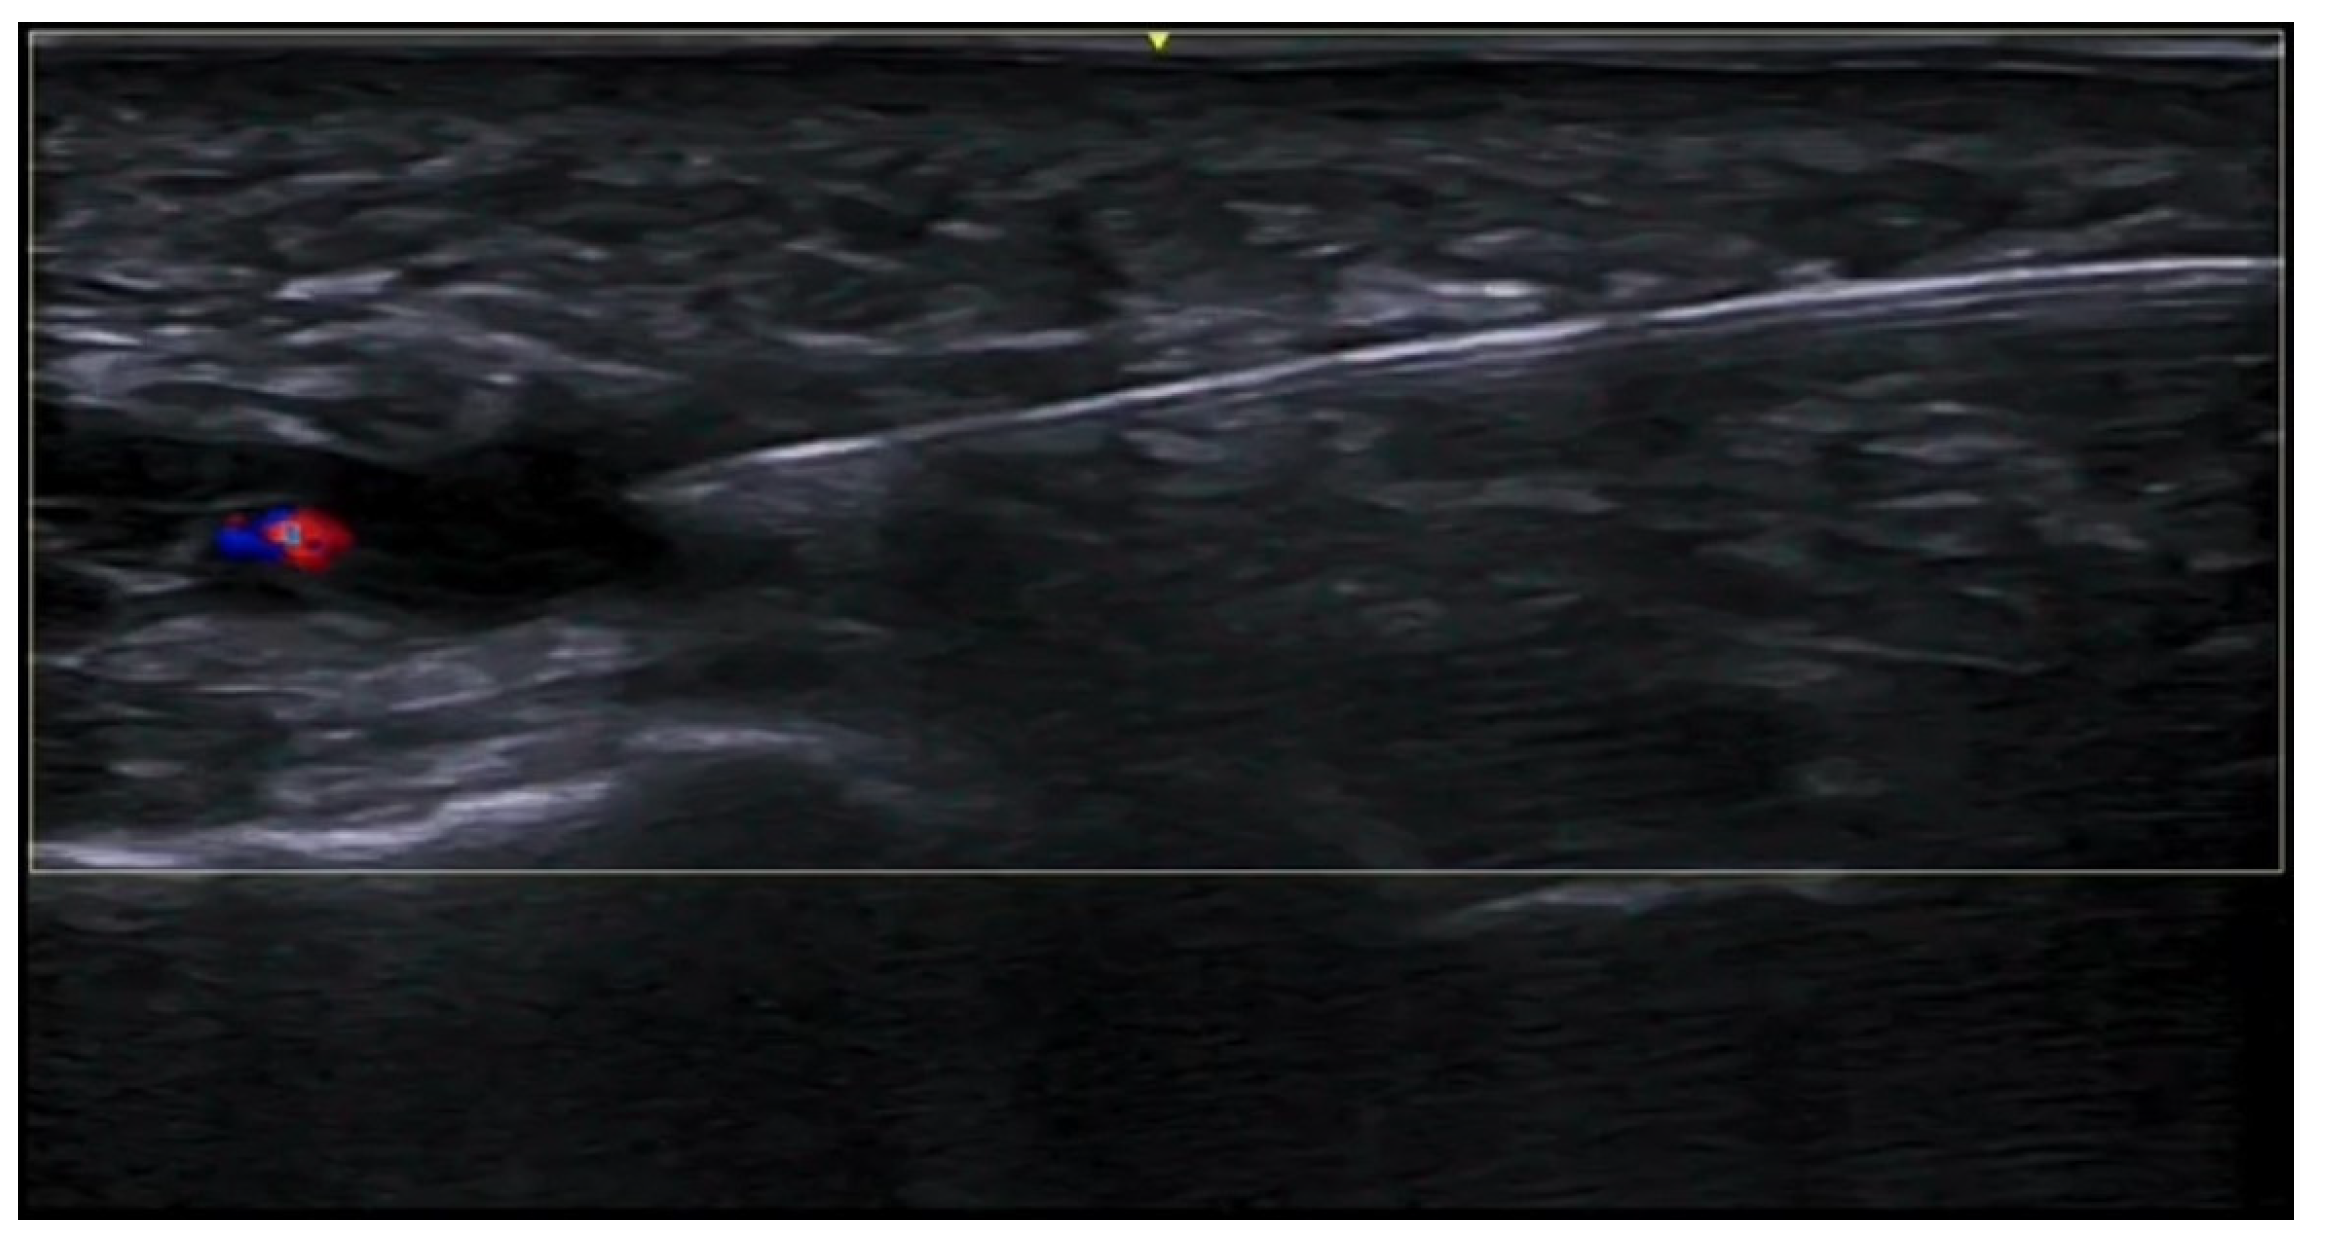

- Velthuis, P.J.; Jansen, O.; Schelke, L.W.; Moon, H.J.; Kadouch, J.; Ascher, B.; Cotofana, S. A Guide to Doppler Ultrasound Analysis of the Face in Cosmetic Medicine. Part 1: Standard Positions. Aesthetic Surg. J. 2021, 41, NP1621–NP1632. [Google Scholar] [CrossRef]

- Vasconcelos-Berg, R.; Izidoro, J.F.; Wenz, F.; Müller, A.; Navarini, A.A.; Sigrist, R.M.S. Doppler Ultrasound-Guided Filler Injections: Useful Tips to Integrate Ultrasound in Daily Practice. Aesthetic Surg. J. 2023, 43, 773–783. [Google Scholar] [CrossRef]